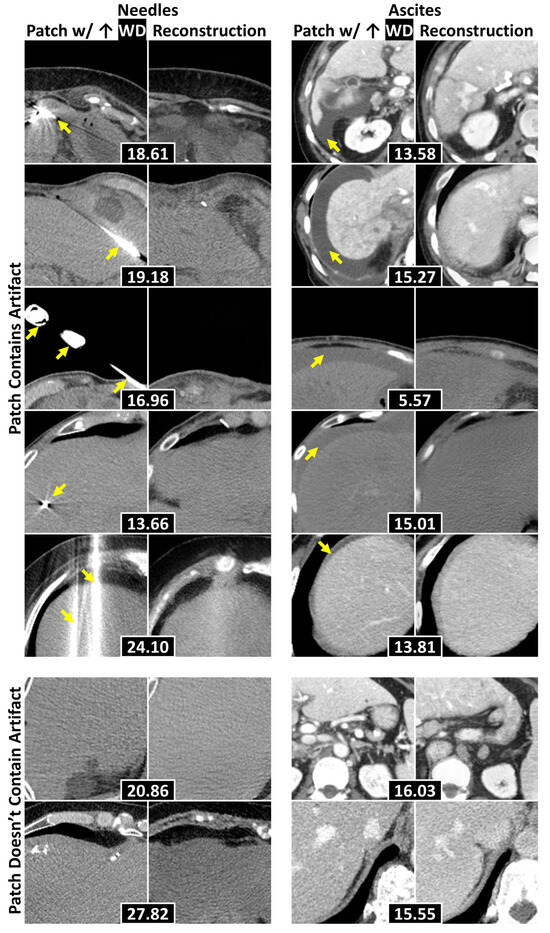

3.4. Localization of Anomalous Regions